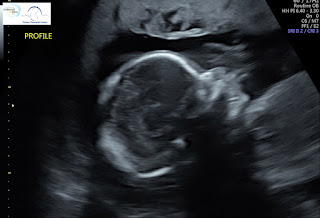

18 weeks after conception (20 weeks LMP), Baby Chris is about the size of a banana at 10 inches long from head to toe and 10 1/2 ounces. Circadian rhythm—the daily cycle of wakefulness and rest—shows up in Baby Chris’s movement and heart rate. You can also spot movement in Baby Chris’s vocal chords as he or she practices the muscle movements that will be necessary to make noise in the outside world.

It’s common for prenatal care providers to offer ultrasounds at this point in pregnancy, so we have an abundance of images this week. Here are just a few. Thank you to everyone who donated!